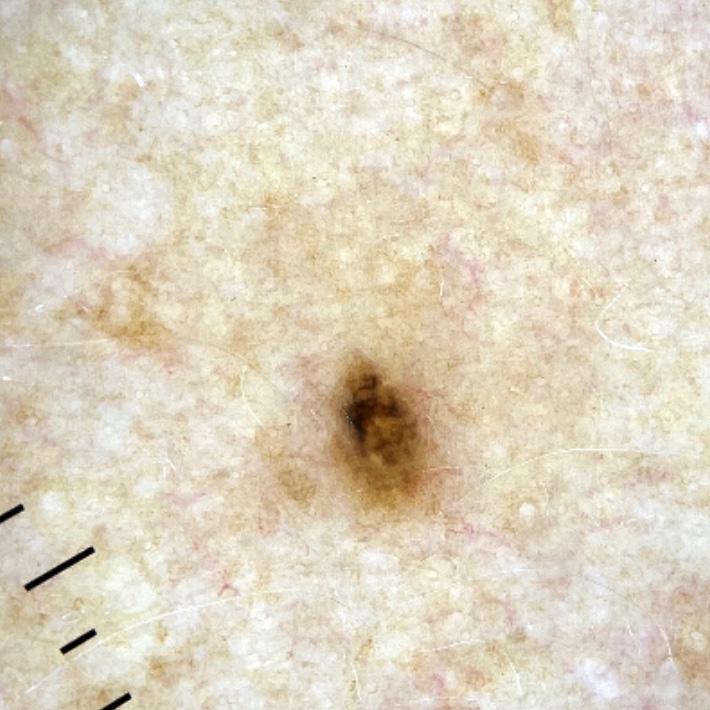

Clinical

Field Value

acquisition_day 207

age_approx 45

anatom_site_1 Upper extremity

anatom_site_general upper extremity

diagnosis_1 Benign

diagnosis_confirm_type single image expert consensus

fitzpatrick_skin_type I

image_type dermoscopic